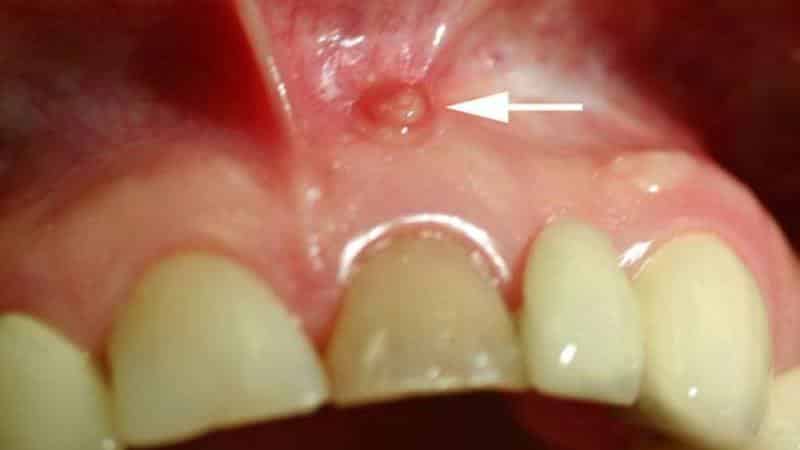

Кисты в полости рта часто встречаются и могут появляться в любом возрасте. Однако их появление может быть незаметным и не вызывать дискомфорта. Иногда пациенты могут испытывать легкое недомогание, такие как покалывания и незначительные покраснения. В таких случаях важно обратиться к врачу. На фото можно увидеть, как выглядит киста в ротовой полости.

Кисты в полости рта — это специфические воспалительные образования, которые имеют форму овальной капсулы. Они окружены соединительной тканью снаружи и покрыты многослойным эпителием внутри. Размеры кист могут быть различными, иногда достигая нескольких сантиметров. Они образуются в области десны, ближе к корню зуба. Вначале образование не проявляет себя и формируется из мягких тканей. Только со временем оно заполняется гнойным содержимым.

- появление небольшого пузырька в корневой зоне, который со временем увеличивается и наполняется жидкостью;

В случае тяжелых форм кисты в полости рта, как показано на фотографии ниже, она может быть легко обнаружена при обычном визуальном осмотре пациента. Внешне она выглядит как большой мешок, наполненный гнойным содержимым. Обратите внимание на фотографию кисты на небе во рту.